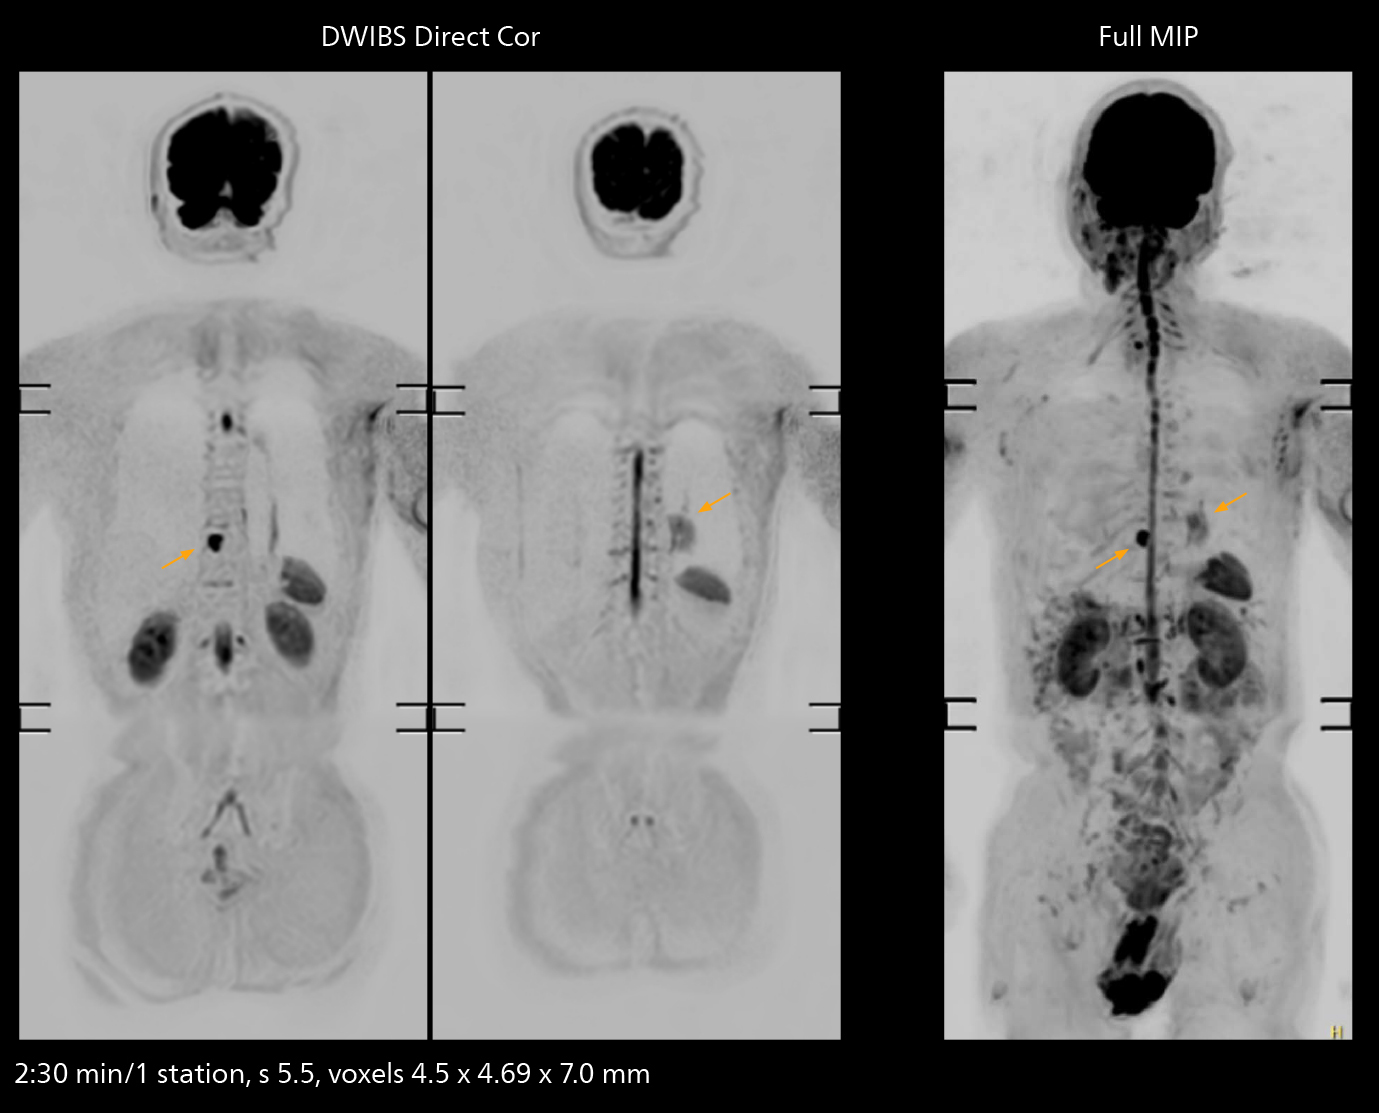

Fast whole body DWIBS examination

With SmartPath to Elition X the team can obtain excellent quality DWIBS imaging and reduce imaging time. Other sequences also fit in the examination slot. This case shows left paravertebral neurogenic tumor and Th10 vertebral hemangiomas.

The value of the Elition X gradients is also evident in DWIBS studies. “The fact that we can consistently obtain distortion‐free DWIBS while reducing imaging time at three coronal stations is excellent,” Dr. Makuuchi says. “In these patients, it’s also important that the application of Compressed SENSE to T2‐weighted, STIR and mDIXON sequences has no impact on the examination time of whole‐body imaging. As a result of the increased speed and higher image quality we realize, DWIBS studies have now become routine examinations.”